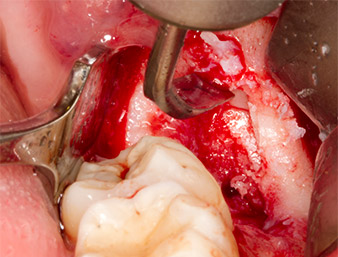

To obtain autogenous material for subsequent wound treatment, healthy bone chips were harvested from the surroundings of the root remnant with a piezo surgical instrument (Piezomed B5) (Fig. 5).

The autogenous tissue was removed with the scraper-shaped section of the working part of the instrument and stored in a physiological saline solution until further use (cf. Fig. 13).